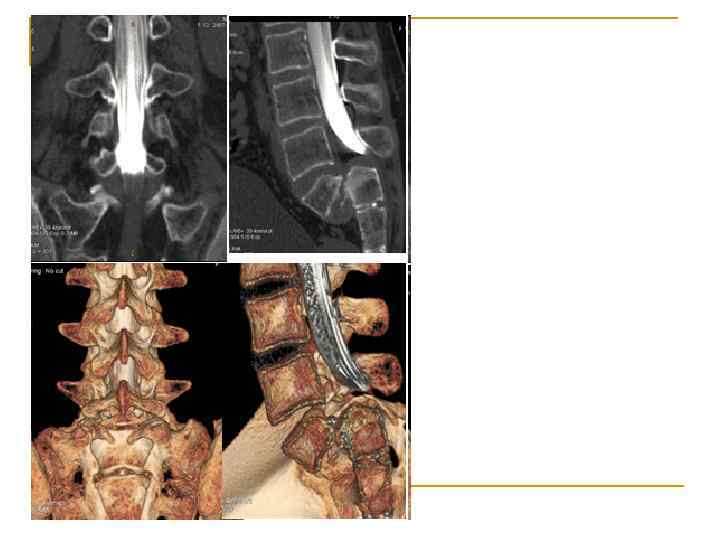

Клинико-физиологические методы исследования функций нервной системы n 1. 2. 3. 4. Лучевые Рентгеновская компьютерная томография (КТ, СК, МСКТ) Магнитно-резонансная компьютерная томография (МРТ) Однофотонная КТ (ОФЭКТ) Позитронная эмиссионная томография (ПЭТ)

Вопрос 1. 5 Компьютерная рентгеновская томография головного мозга Физиология человека Под редакцией В. М. Покровского, Г. Ф. Коротько Медицина, 2003 (2007) г. Страница 97 -98.

Спиральный компьютерный томограф Hi. Speed NX/i фирмы «General Electric»